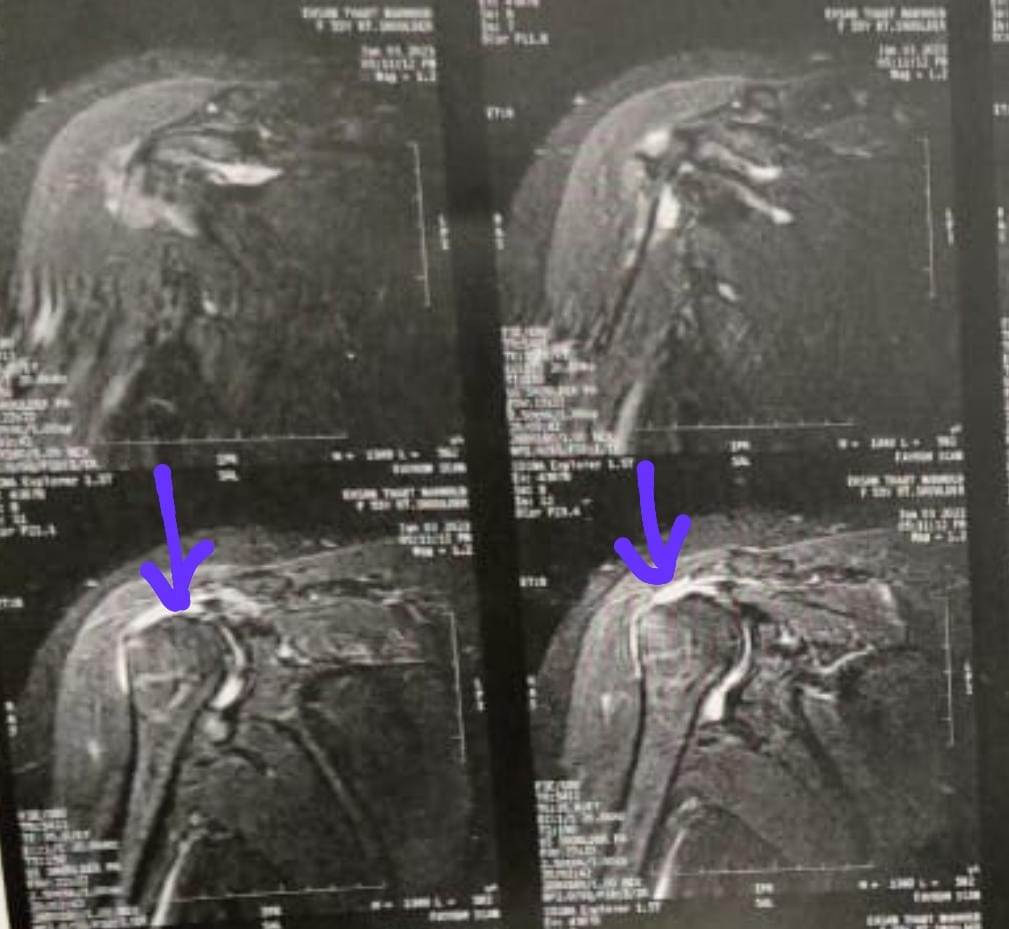

ومن جهة أخرى.. قام الدكتور أحمد إبراهيم سالم بإجراء عدد ٤ جراحات بالمنظار لعلاج مختلف إصابات الكتف مثل قطع أوتار الاسورة الدوارة للكتف وتمدد محفظة الكتف نتيجة الخلع المتكرر، وتمت متابعة المرضى لمدة ٦ أسابيع من التأهيل والعلاج الطبيعى حتى عادوا لممارسة الحياة اليومية بشكل طبيعى وبمجال حركى مقبول بدون ألم.